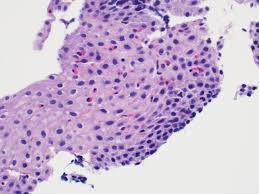

Although hsv esophagitis is much more common in immunosuppressed individuals, it can occur in healthy persons. Patients typically present with odynophagia, dysphagia, and retrosternal chest pain. We here present a case of hsv esophagitis that was presented with its characteristic features. Differential diagnosis between herpes simplex virus (hsv) esophagitis and cytomegalovirus (cmv) esophagitis is challenging because there are many similarities and overlaps between their endoscopic features. Esophagitis due to herpes simplex virus (hsv) infection1,2. Less common causes of esophagitis and esophageal injuryand esophageal anatomic anomaliesseptember 16, 2009. This form of esophagitis typically occurs when. Herpes esophagitis is a viral infection of the esophagus caused by herpes simplex virus (hsv). Alimentary tract pathology in infants and children. Eosinophilic esophagitis title pathology reviewptyp loattrfree full text sb. Densely matted pseudohyphae and budding spores in squamous debris, fibrinopurulent exudate or necrotic debris. Common forms of esophagitis include reflux esophagitis, infectious esophagitis, pill esophagitis, eosinophilic esophagitis, and radiation and chemoradiation esophagitis. Causes of esophagitis include stomach acids backing up into the esophagus, infection, oral medications and allergies.

Although hsv esophagitis is much more common in immunosuppressed individuals, it can occur in healthy persons. This guide is not intended to be used as a textbook. Densely matted pseudohyphae and budding spores in squamous debris, fibrinopurulent exudate or necrotic debris. Common forms of esophagitis include reflux esophagitis, infectious esophagitis, pill esophagitis, eosinophilic esophagitis, and radiation and chemoradiation esophagitis. Esophagitis due to herpes simplex virus (hsv) infection1,2.

Differential diagnosis between herpes simplex virus (hsv) esophagitis and cytomegalovirus (cmv) esophagitis is challenging because there are many similarities and overlaps between their endoscopic features. Dysphasia and odynophagia are common symptoms with advanced hiv. Esophagitis is the inflammation or irritation of the esophagus. Common forms of esophagitis include reflux esophagitis, infectious esophagitis, pill esophagitis, eosinophilic esophagitis, and radiation and chemoradiation esophagitis. This guide is not intended to be used as a textbook. The results of one survey suggested there may be regional variation, with a. Virtual international pathology institute (vipi). Candida esophagitis (see the image below) is the most common type of infectious esophagitis.